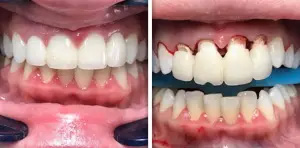

Periodontics